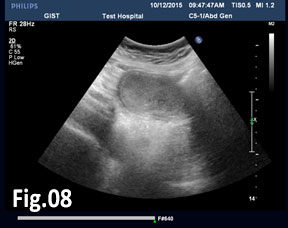

GISTs are rare mesenchymal neoplasms of the digestive tract [1,2]. They have been documented in all parts of the gastrointestinal tract, but are most common in the stomach and small intestine, followed by colo-rectum, mesentery, and esophagus [1,2]. However, the synchronous occurrence of lung cancer and GIST is extremely rare [3]. The incidence of GIST coexisting with additional malignancies is 9% to 27%, and primary lung cancer in GIST patients is 0.5%-1.2% [3]. A 75 year old woman with a smoking history for >30 years was diagnosed with advanced stage of left lung primary adenocarcinoma by chest computed tomography (CT) and bronchoscopy with sampling in February 2015 (Fig.1, Fig.2). The patient started Erlotinib 150 mg/day. In September 2015 the patient was admitted with vague abdominal pain and postprandial vomiting. Physical examination, routine blood, urine and stool investigations were unremarkable. Abdominal ultrasound detected an oval, homogenous, hypoechoic lesion 6/5/4 cm, arising from the submucosal layers of the gastric wall (Fig 3). The color Doppler demonstrated neovascularization (Fig 4). Except for 3 small simple liver cysts, no other abnormalities were present. Upper endoscopy and endoscopic ultrasound (EUS) revealed a large oval, slightly lobulated mass, hypoechoic 6x5cm between incisura angulars and greater curvature of the gastric body, originating from the 4th layer of the wall (muscularis propria). The tumor was slightly “dumbbell” shaped, protruding in and outside the stomach lumen, with several irregular hypoechoic zones and micro cysts within, looked encapsulated without infiltration of the surrounding tissues and pathologic abdominal lymph nodes (Fig. 5). A contrast-enhanced ulstrasound (CEUS) and contrast-enhanced computed tomography (CECT) of the abdomen additionally characterized the lesion and excluded liver metastases. (Fig. 6, Fig. 7) Percutaneous true-cut biopsy of the lesion was performed (18G, two separate puncture sites) (Fig 8). The immunohistochemical analysis revealed epithelioid-type GIST, diffusely positive for c-kit (CD117), with a weak focal expression of S-100 (Fig. 9). Due to life expectancy defined by the unresectable advanced lung cancer, the patient was not indicated for resection of the gastric GIST. Imatinib (Glivec) 400 mg/day was started as a “co-therapy” to Erlotinib in November 2015. After 12 months of co-treatment, a good control of both tumors was achieved. CT and abdominal ultrasound showed the gastric lesion was slightly shrunk on therapy, with large central necrosis (Fig. 10). The patient is being followed up.

Figure 8: A true-cut biopsy of the lesion - 18G, two separate puncture sites.